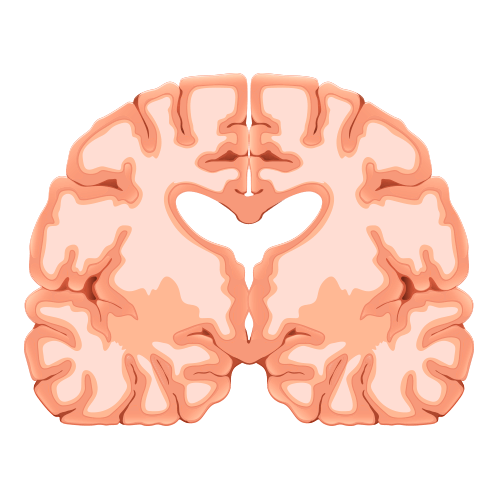

Impacto do Alzheimer no cérebro saudável